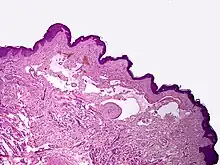

Cavernous lymphangioma, H&E stain. Irregular, dilated spaces are visible in dermis.

Lymphangiomas have traditionally been classified into three subtypes: capillary and cavernous lymphangiomas and cystic hygroma. This classification is based on their microscopic characteristics. A fourth subtype, the hemangiolymphangioma is also recognized.[9]

Cavernous lymphangiomas

Composed of dilated lymphatic channels, cavernous lymphangiomas characteristically invade surrounding tissues.